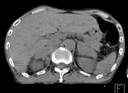

Ca lâm sàng 3: Bệnh nhân Nguyễn X.T., nam, 58 tuổi. Chẩn đoán: U lympho ác tính không Hodgkin, GPB: WF6. Hình PET cho thấy tổn thương ở phổi, hạch, xương, tuyến thượng thận hai bên (mũi tên). Hình CT và PET/CT cho thấy tổn thương tăng hấp thu FDG tại vị trí tuyến thượng thận hai bên (mũi tên).